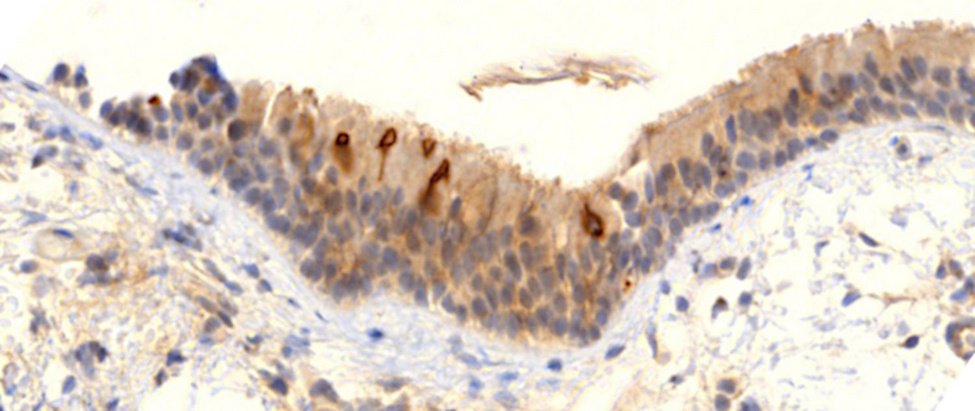

L’infiltrazione linfocitica, l’infiammazione e la distruzione sono state osservate anche in molti altri organi, tra cui cervello, fegato, milza e ghiandole multiple. Tuttavia, invece di illustrarli tutti, concluderemo l’evidenza patologica con un altro risultato immunoistochimico, che mostra in modo sorprendente la lunga durata dell’espressione della proteina spike.

La diapositiva mostra un campione di mucosa bronchiale, di un paziente che è vivo ma ha sofferto di sintomi respiratori da quando è stato vaccinato. Vediamo diverse cellule nello strato cellulare superiore che esprimono fortemente la proteina spike, e questo anche nove mesi dopo la sua più recente iniezione di vaccino! Sebbene questo sia davvero il caso più estremo di espressione di lunga durata, ci sono prove sia dalle autopsie di Burkhardt che da studi pubblicati su campioni di sangue [ 7 ] o biopsie linfonodali [ 8 ] per indicare che l’espressione dura diversi mesi.